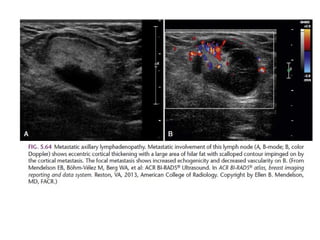

LEFT: Fibroadenoma with non-enhancing septations.

RIGHT: Invasive carcinoma with enhancing septations